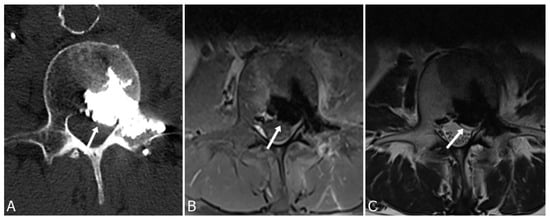

3.1. Epidural and Foraminal Cement Leakage